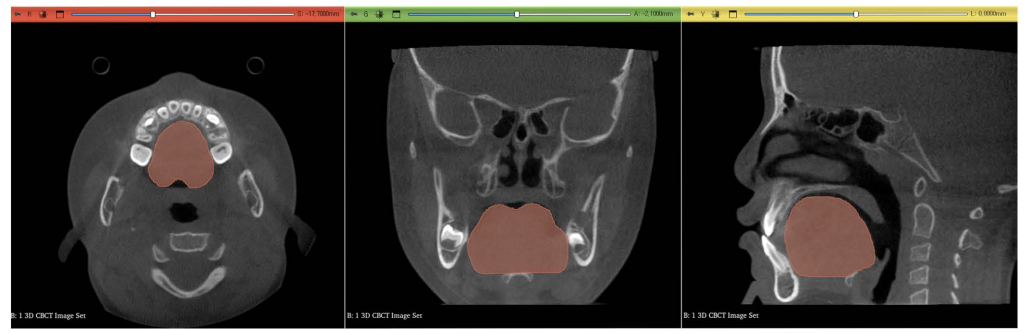

이에 연구팀은 185명의 성인을 대상으로 CBCT를 통한 3차원 영상을 통해 얼굴 뼈 모양과 혀의 위치를 분석했다.

그 결과 턱이 앞으로 나와 보이는 '주걱턱'은 혀가 아래쪽에 있거나 혀 자체가 큰 경향이 있는 것으로 파악됐다. 주걱턱 경향을 나타내는 수치가 낮아질 때(심할 때) 혀끝 위치가 낮았고 동일 수치가 높을수록 혀의 부피는 큰 것으로 나타났다.

턱이 길어 보이는 얼굴형을 가진 사람들은 혀끝이나 혀의 뒤쪽 부분이 상대적으로 낮게 위치하는 경향이 확인됐다. 얼굴 길이가 길수록 혀끝 위치와 혀 뒤쪽 위치도 낮은 것으로 나타났다.

혀의 부피는 치아의 폭과도 관련이 있다. 이번 연구에서 혀의 부피가 클수록 때 △위쪽 어금니 사이 △아래쪽 어금니 사이 △아래쪽 앞니 사이의 폭이 컸다. 혀끝이 아래쪽에 있을수록 위쪽 앞니 사이의 폭은 좁아지고, 위아래 어금니 사이의 폭은 넓어지는 경향도 발견됐다.